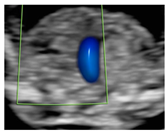

Figure 1.

Case of disagreement in the characterization of color Doppler pattern on the 3VTV between operators 1 and 2 in a case of Ebstein anomaly at 12 + 6 weeks’ gestation. (A,B) show different frames of a videoclip of the 3VTV. (A) Operator 1 observed an abnormal 3VTV pattern in terms of “abnormal vessel number”; (B) operator 2 characterized the same case as with “abnormal vessel dimensions”. AoA, aortich arch; T, trachea; arrow, small pulmonary artery.